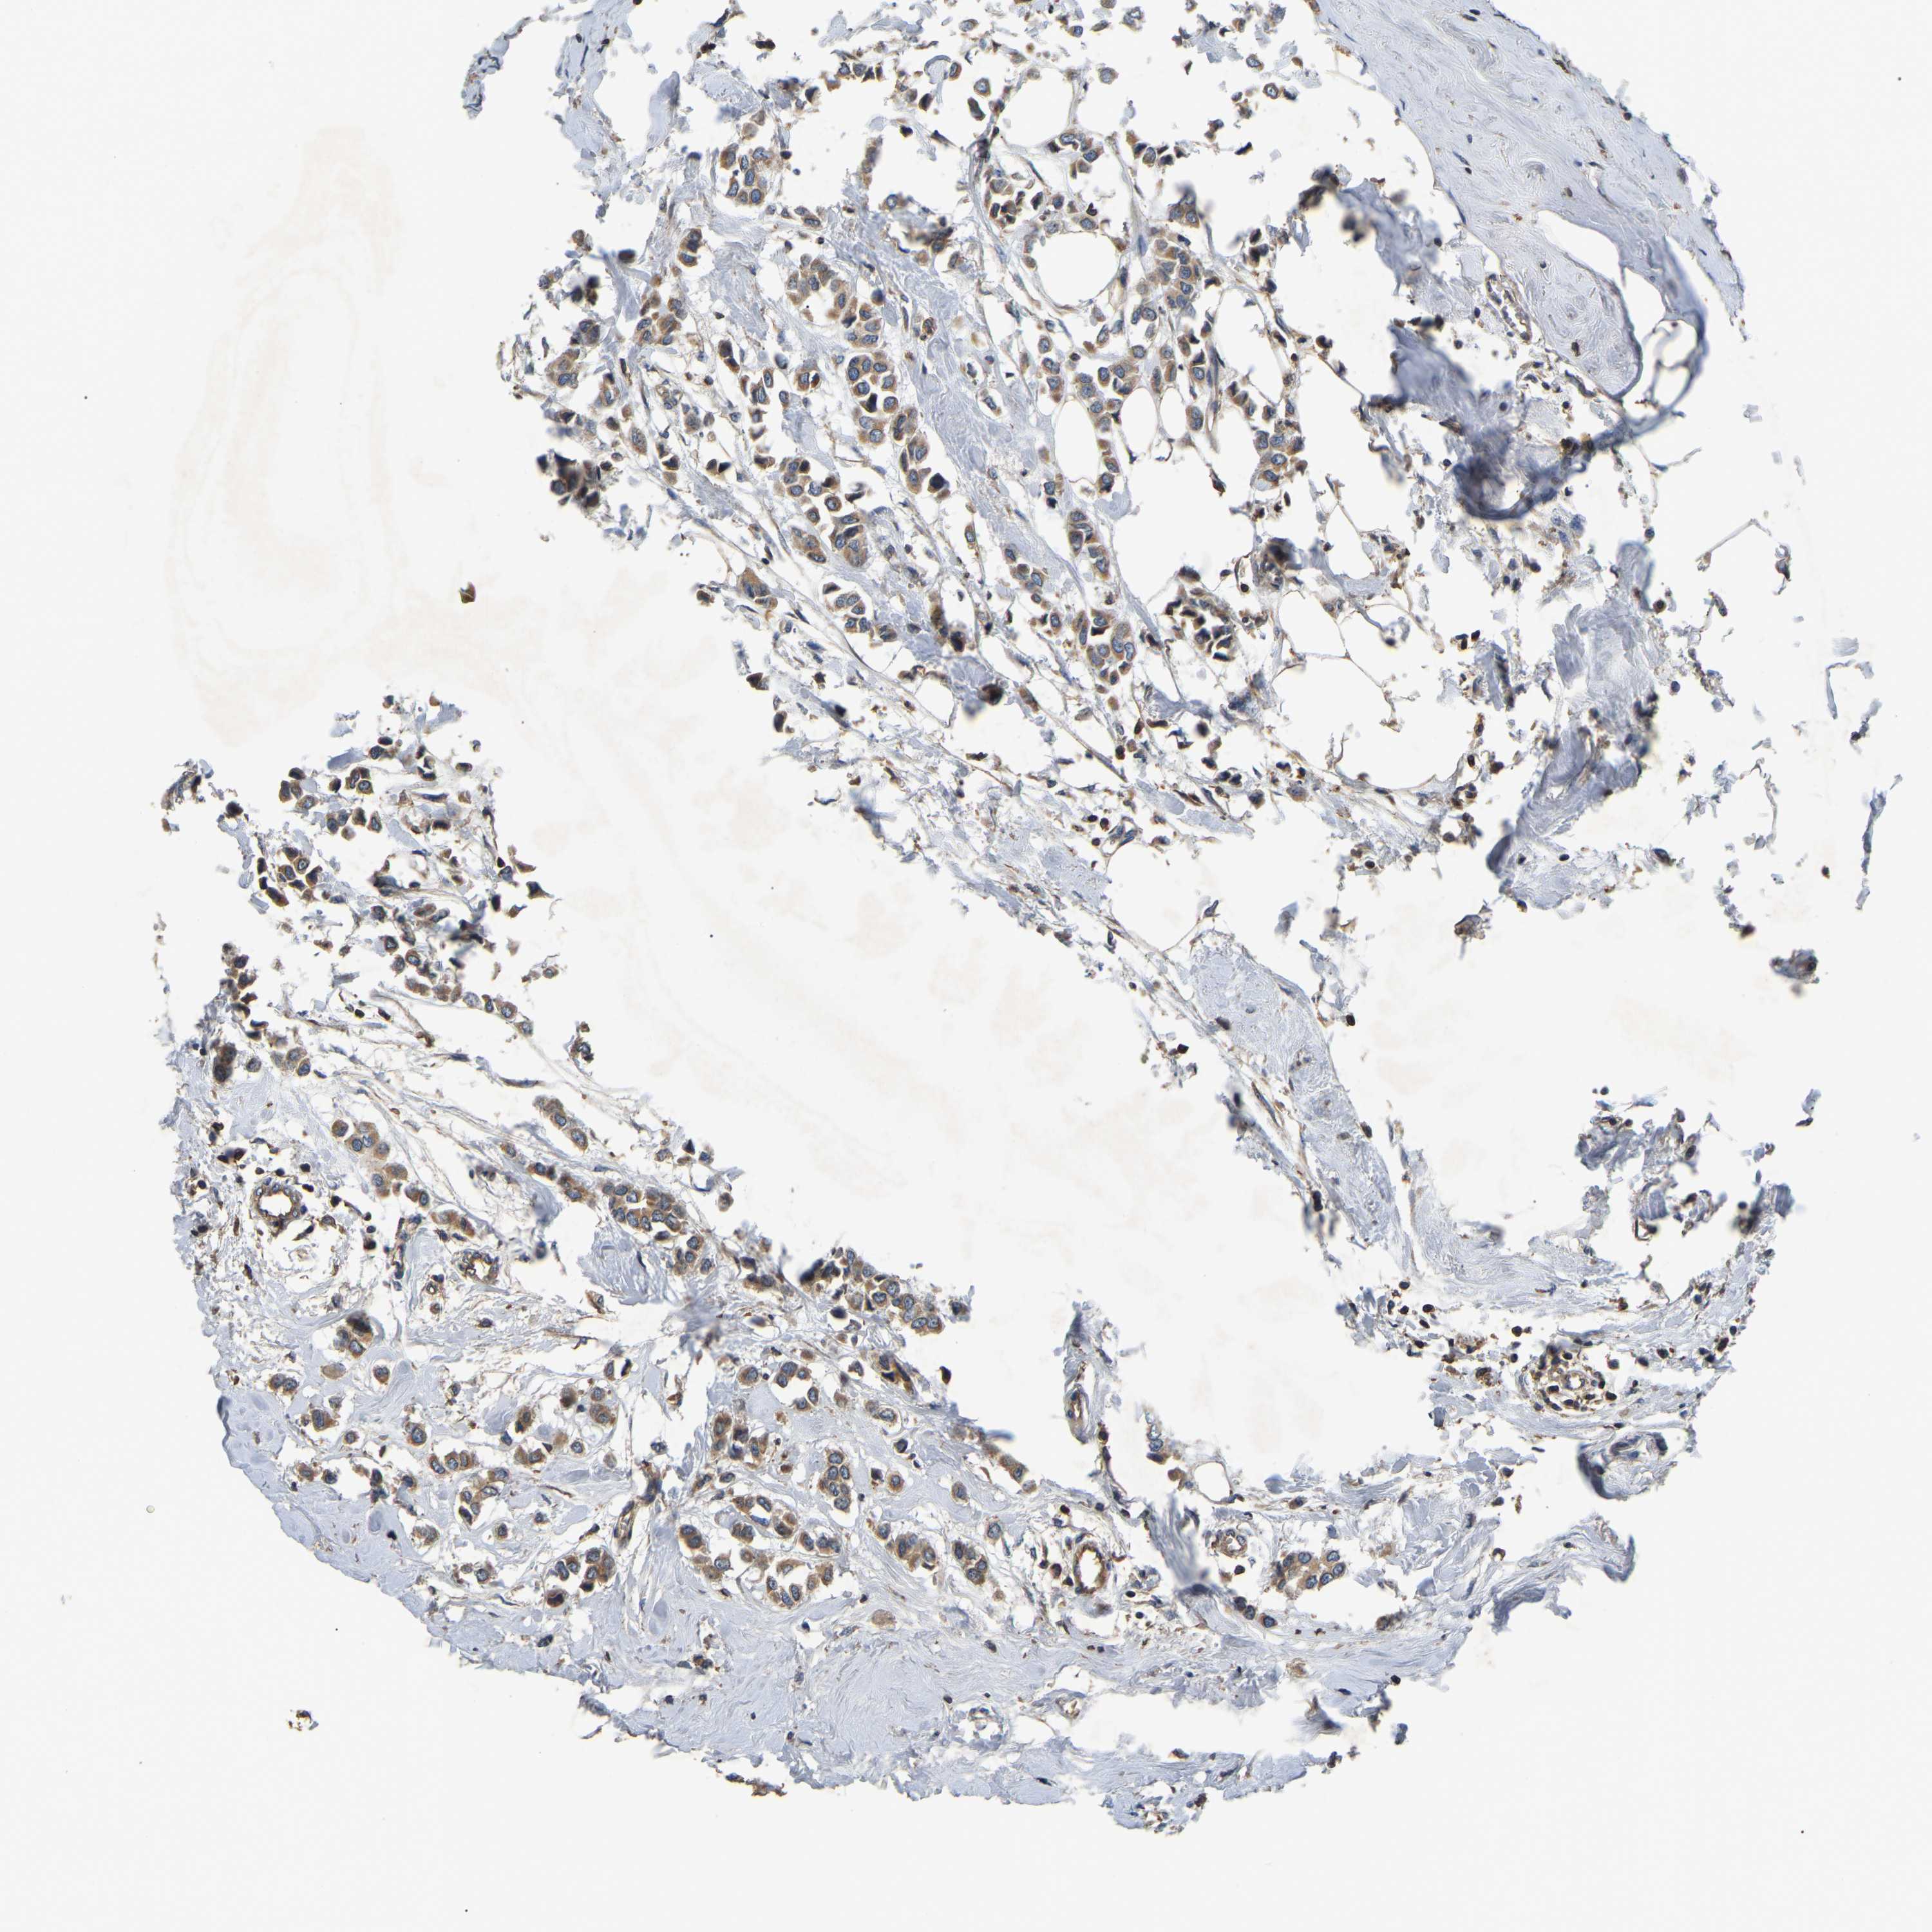

BRCA TCGA BRCA VALIDATION PROTEIN EXPRESSION

Breast cancer

Human cancer